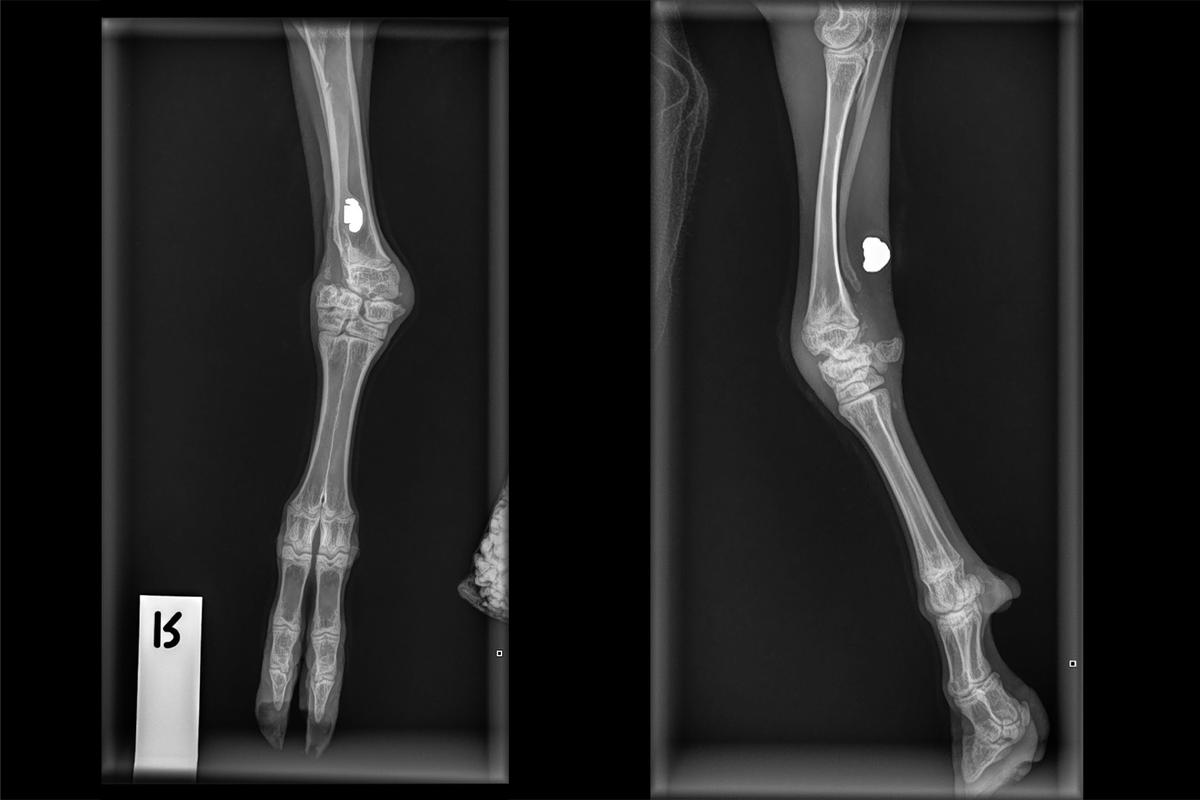

As a result, our vets obtained some x-rays of Frog’s front leg – and found quite a surprise. There was a bullet in her leg that had never been removed, and the limb had healed around it. There was no evidence of any previous vet treatment to address her injury.

Frog's x-rays, showing the bullet in her leg.

While Frog still had mobility and wasn’t in any pain, the long-term prognosis for her injury was debilitation of the joint, and eventual loss of function. Since she was such a small goat and would not grow much bigger, the team decided that amputation would be the best course of action for her. Frog began her journey of rehabilitation and recovery, learning how to get around on three legs.